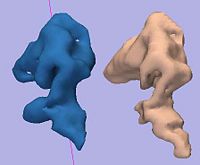

Non Parametric Clustering for Biomolecular Structural AnalysisHigh accuracy imaging and image processing techniques allow for collecting structural information of biomolecules with atomistic accuracy. Direct interpretation of the dynamics and the functionality of these structures with physical models, is yet to be developed. Clustering of molecular conformations into classes seems to be the first stage in recovering the formation and the functionality of these molecules. More... New: X. LeFaucheur, E. Hershkovits, R. Tannenbaum, and A. Tannenbaum. Non-parametric clustering for studying RNA conformations. IEEE Trans. Computational Biology and Bioinformatics, volume 8, 2011, pp. 1604-1618. New: Il Tae Kim, A. Tannenbaum, R. Tannenbaum. Anisotropic conductivity of magnetic carbon nanotubes embedded in epoxy matrices. Carbon, volume 49, 2011, pp. 54-61. |